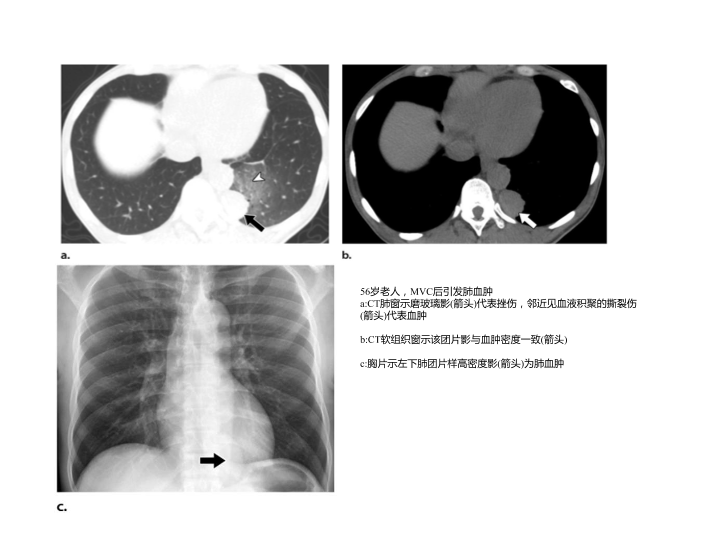

胸部外伤及胸腔积液处理